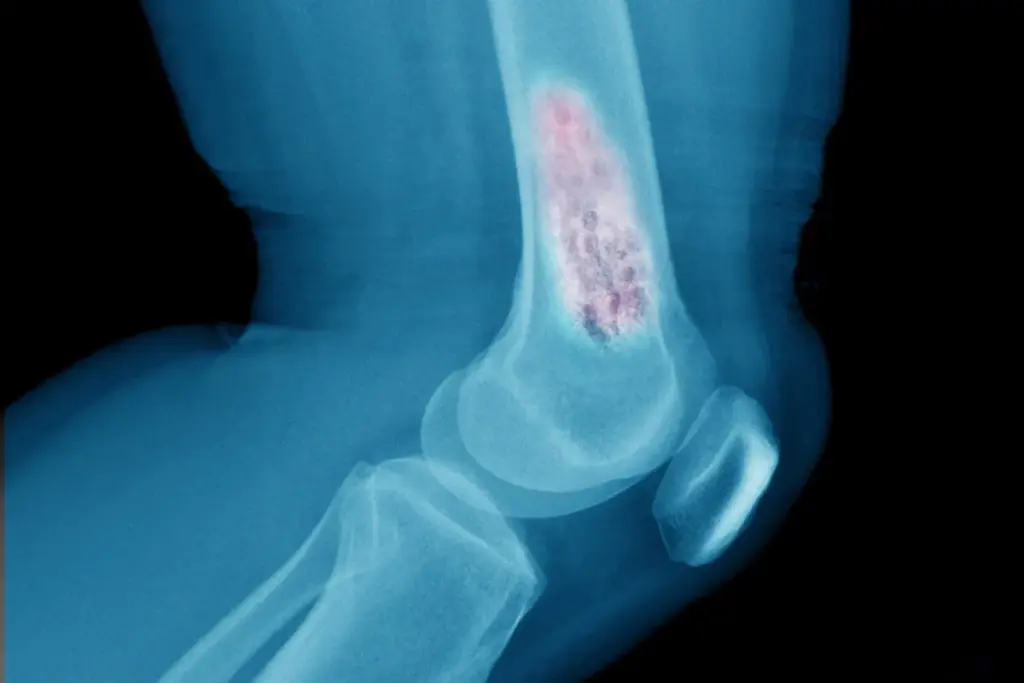

How Do Imaging Tests Reveal Bone Damage?

Myeloma cells can weaken bones, causing “lytic lesions” (soft spots) or fractures that might not be immediately painful. Accurate imaging helps us see the extent of the disease throughout the skeleton.

• Low-Dose Whole Body CT: This has largely replaced standard X-rays because it provides a much more detailed 3D view of the bones and can detect smaller lesions.

• MRI (Magnetic Resonance Imaging): An MRI is highly sensitive and is used to detect myeloma in the spine or pelvis, especially if the doctor suspects the cancer is pressing on the spinal cord.

• PET-CT Scan: This combines metabolic and anatomical imaging. It highlights areas of active cancer growth (which light up on the scan) throughout the entire body. It is crucial for determining the stage of the disease and checking how well the treatment is working later on.